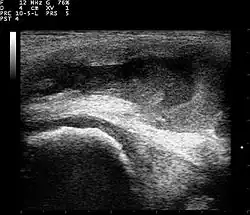

Ultrasound

Ultrasound imaging may be used by your doctor in their office as a diagnostic tool to better visualize the effusion and its size. This can also be an effective tool to guide treatment such as a joint aspiration.[10]